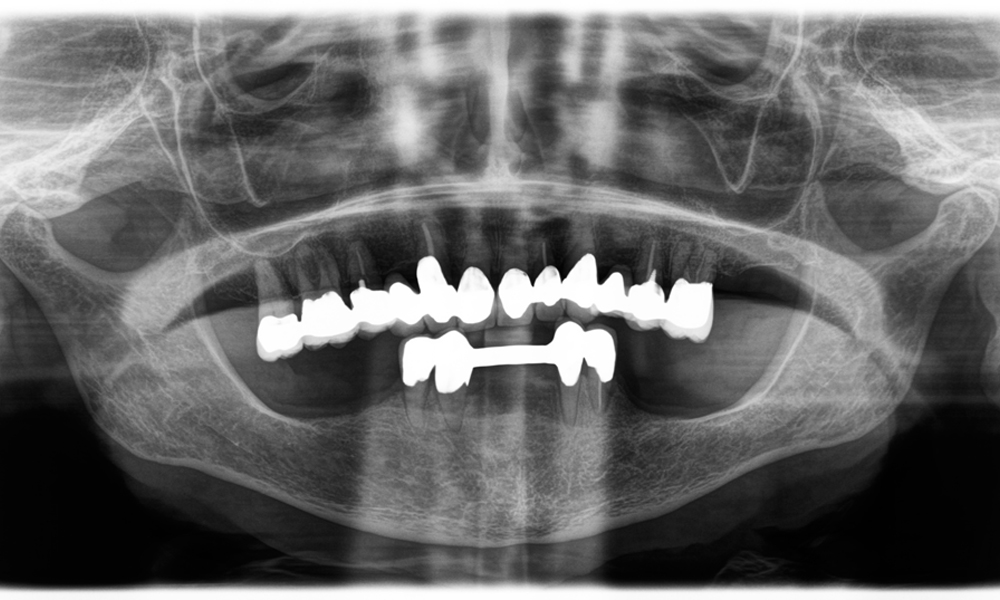

The challenge was to remove twelve splinted crowns made of a base metal alloy without damaging the underlying abutment teeth. The handpiece was used to precisely section the ceramic layers and divide the metal framework using a carbide bur, enabling minimally traumatic crown removal. Within just 30 minutes, the old restorations were removed, allowing for the preparation of a new prosthesis, comprising full-contour zirconia in the posterior region and veneered crowns anteriorly. The result was a complete restoration that delivered both functional and aesthetic success (see Fig. 1).

A jaw x-ray from an 81-year-old patient, in front of a black background.

Figure 1: Aesthetic rehabilitation of PFM crowns: Complete removal and replacement of 40-year-old PFM crowns to improve aesthetics in an 81-year-old patient.